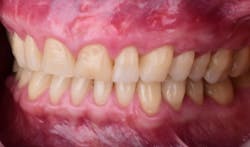

This new biological approach involving blood derivatives A-PRF and I-PRF combined with precision minimally invasive surgery for root coverage demonstrates faster healing without the need of a donor site. The morbidity of GDT is decreased and patient case acceptance is higher compared with traditional grafts. Before-and-after pictures are shown below (figures 15–22).